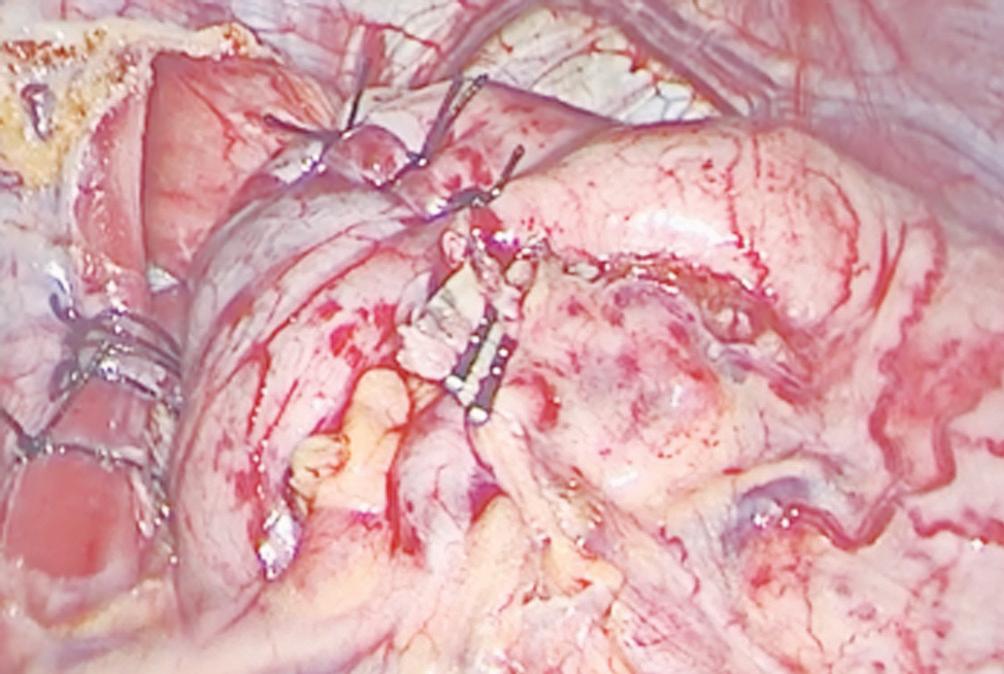

Neoplasia sólida pseudopapilar de páncreas: diagnóstico y manejo quirúrgico en una paciente joven

Elías Lessin García Alba, Magalí Chahdi Beltrame, Natalia Soledad Ruíz, Gabriel Cervantes, Marcelo Enrique Lenz Virreira, Francisco Juan Mattera, Emilio Gastón Quiñonez

Santiago Bustince, Nicolás H Dreifuss, Marcelo F Amante, Lucas McCormack, Pablo Capitanich

Pancreatic Atypical Neurofibromatous Neoplasm with Uncertain Biological Potential (ANNUBP) Mimicking a Solid Pseudopapillary Tumor Pancreatic ANNUBP